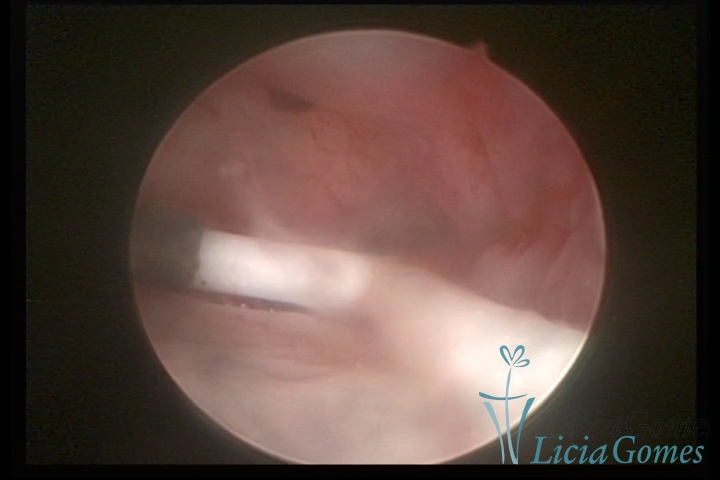

Cicatriz de cesárea com fio de sutura, não absorvido, como corpo estranho

×